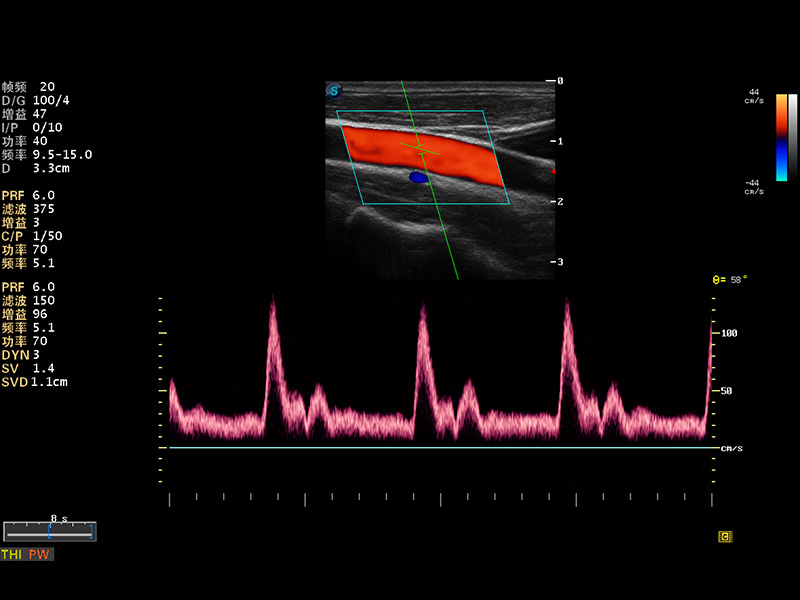

S8 EXP便携式彩色多普勒超声诊断仪是银河集团官网研发的高端全身应用型便携彩超。高通道的VIS平台融合可视化(Visual)、智能化(Intelligent)和人性化(Smart)的特点,配以银河集团官网自主研发生产的探头大家族,使您能够快速、准确的获得病人信息,提高工作效率的同时减轻疲劳。

多波束形成器

谐波成像